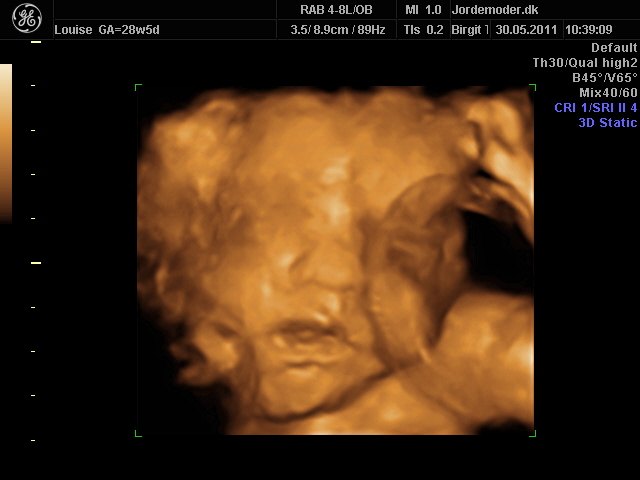

Moar2011

i uge 28

Vedhæftede fotos (klik for at se i fuld størrelse)